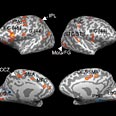

חברי צוות המחקר הצליחו, לראשונה, לזהות אזורים מוגדרים במוח שמופעלים באופן ייחודי בתגובה לתנועה שכפופה לחוק התנועה במסלולים עקמומיים. ממצא זה מראה כי "חוק השני שלישים", המתבטא הן בביצוע תנועות פיסיות והן בתפיסה חזותית של תנועה במסלולים עקמומיים, נובע ממנגנונים עצביים הפועלים במוח, ואינו רק תוצר לוואי של פעילות השרירים, כפי שסברו בעבר. המדענים מניחים, כי מנגנונים אלה משפיעים בין השאר על האופן שבו אנו מתכננים מראש תנועות מוטוריות. ממצאים אלה פורסמו באחרונה בכתב-העת המדעי "רשומות האקדמיה למדעים של ארה"ב" (PNAS).

המדענים השתמשו בדימות תיפקודי מוח בתהודה מגנטית, fMRI, מערכת המאפשרת מעקב אחר פעולותיו של מוח הנבדק

בזמן כמעט אמיתי. הם שינו את ניסוי האליפסות, כך שהמתנדבים שהיו נתונים בתוך מערכת ה-fMRI התבקשו לצפות בענן נקודות שנעו במסלול אליפטי לפי התסריטים של הניסוי הקודם. כדי לוודא שממצאי הניסוי אינם נובעים מהבדלים בתנועות העיניים, התבקשו הנבדקים להימנע ממעקב פעיל אחר תנועת ענן הנקודות.

בחלק מתנאי הניסוי אף נוטרו תנועות עיניהם באמצעות מיכשור מיוחד. באמצעות מעקב אחר המתחולל במוחם של הנבדקים כשהם מבצעים את המטלה הזאת, הצליחו המדענים למפות את אזורי המוח שהיו פעילים בזמן ביצוע המטלה. כך התברר, שהאזורים המעורבים בעיבוד חוק התנועה במסלולים עקמומיים בעת פעילות חזותית (מעקב אחר נקודות נעות על מרקע מחשב), הם אותם אזורים הממלאים תפקיד בתכנון וביצוע של תנועות מוטוריות.